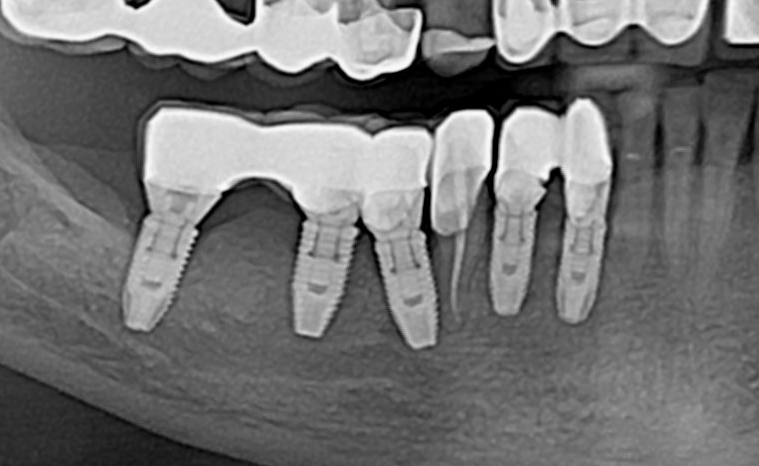

kramer Опубликовано 15 апреля, 2021 Поделиться Опубликовано 15 апреля, 2021 Пациентке летом 2018 г установили имплантаты, какие-то одномоментно, какие-то нет, не помнит. Коронки через 3 месяца, цементная фиксация. Вскоре после этого начались жалобы на боль, дискомфорт в области всех имплантатов, особенно 42 и 43. Лечащий врач контрольных снимков не делал, утверждал, что все в порядке. Обратилась к нам, на ОПТГ признаки резорбции кости в обл. имплантата 43 и апикально у импл. 46. Посоветовал ей подойти с этим снимком к своему врачу. Далее с ее слов врач демонтировал коронки 42-43, что-то там чистил (цемент?), зафиксировал обратно (причем как видно, одна из коронок не досела). Новый снимок от 15.04.21 - как-будто ничего и не было. Жалоб сейчас тоже нет. WTF? 2 Ссылка на комментарий

Дмитрий Л. Опубликовано 15 апреля, 2021 Поделиться Опубликовано 15 апреля, 2021 Предположу, что апикальный участок - зажившие периапикальные изменения, а периимплантит в обл премоляров вызван непассивной посадкой коронок изначально, потом коронки недосели, но давления на импланты не оказывают. Как бы там ни было, протетику на премолярах стоит переделать. 1 Ссылка на комментарий